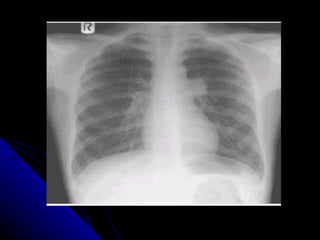

PAQUIPLEURITIS

DERRAME TABICADO